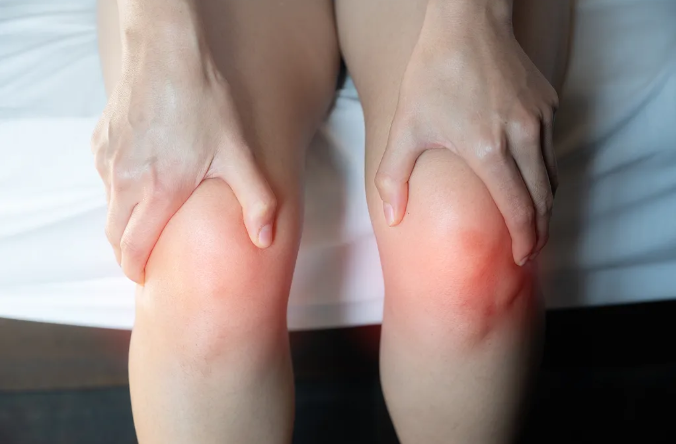

痛风痛风,来去如风。痛风常常在夜间或清晨突然发作,疼痛感像刀割,最常被“袭击”的部位是大拇趾,脚踝、膝盖、手腕、手指等关节也可能中招。发作时,患处会迅速变得红肿,摸上去发烫。

如果长期不控制,血液中过高的尿酸会形成“痛风石”,可能导致关节畸形、活动受限。